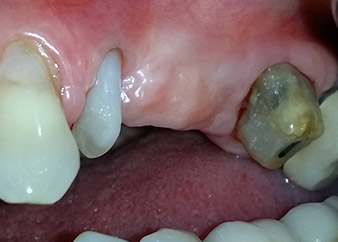

Un mese più tardi, nel giorno programmato per l'intervento, il dolore e l'infiammazione in corrispondenza del dente 24 erano minimi, ma era ancora presente mobilità di classe 2 secondo Miller. Dopo l'apertura dei lembi e la pulizia del tessuto periapicale e periradicolare infetto, l'estensione della mancanza ossea si è resa evidente (Figg. 2 e 3).

Tutto il tessuto osseo vestibolare e distale era mancante in corrispondenza della radice buccale. La possibilità di attacco era essenzialmente ristretta alla radice palatale, evidenziando la prognosi negativa preliminare. Anche il dente 27 mostrava un punto di attacco orizzontale ridotto e una rarefazione apicale minima (cfr. Fig. 1), senza sintomi clinici.